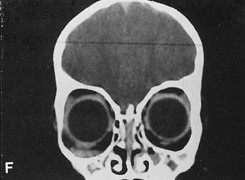

Fig. 14. A,B. Large intraorbital lymphangioma causing proptosis and optic nerve compression in a 2-year-old child. C. View of the left orbit from above after removal of the frontal bone flap, including the supraorbital rim and orbital roof. An extensive exposure of the entire superior and lateral orbit is afforded. The levator and superior rectus complex is being retracted laterally with a muscle hook, whereas the Freer elevator retracts the superior oblique muscle medially. The frontal nerve can be seen running from posterior to anterior over the superior orbit. The orbital mass is exposed in this fashion. D. The fronto-orbital bone flap is wired back in place after completion of the procedure. E. Postoperative appearance of the patient. F. The postoperative CT scan shows complete removal of the lymphangioma. This large and diffuse lesion would have been difficult to remove with any other approach.